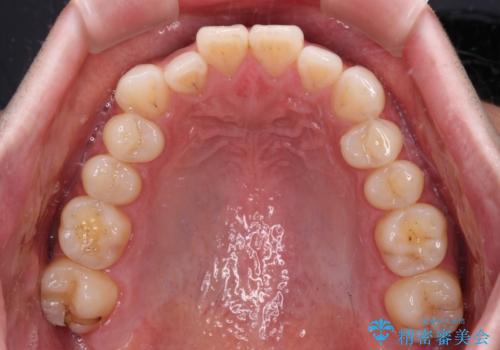

- 上下顎歯列のデコボコを改善したいとのことで来院された患者様です。

自己管理の大変なインビザラインや、目立つ表側のワイヤー矯正は避けたいとのことで、

上顎だけ裏側装置のハーフリンガルにて矯正しました。

一年と数か月で矯正を終えることができました。

下顎前歯部には後戻り防止のワイヤーを装着しています。